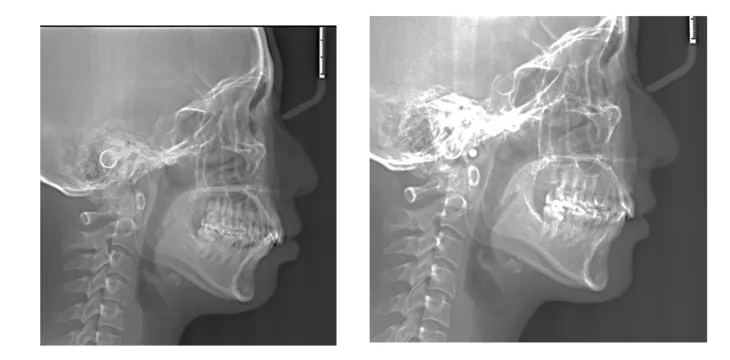

病例展示: